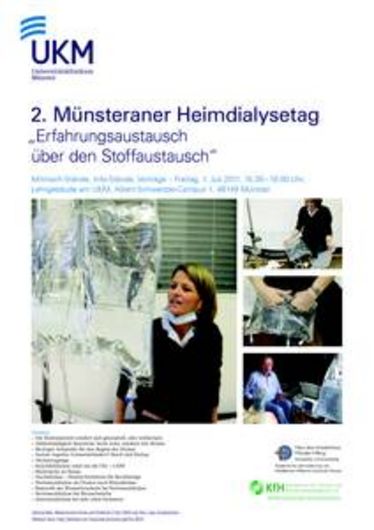

24. Arbeitstagung Psychonephrologie

24. Arbeitstagung Psychonephrologie

24. Arbeitstagung Psychonephrologie

24. Arbeitstagung Psychonephrologie

Workshop Peritoneal-Dialyse

Workshop Peritoneal-Dialyse